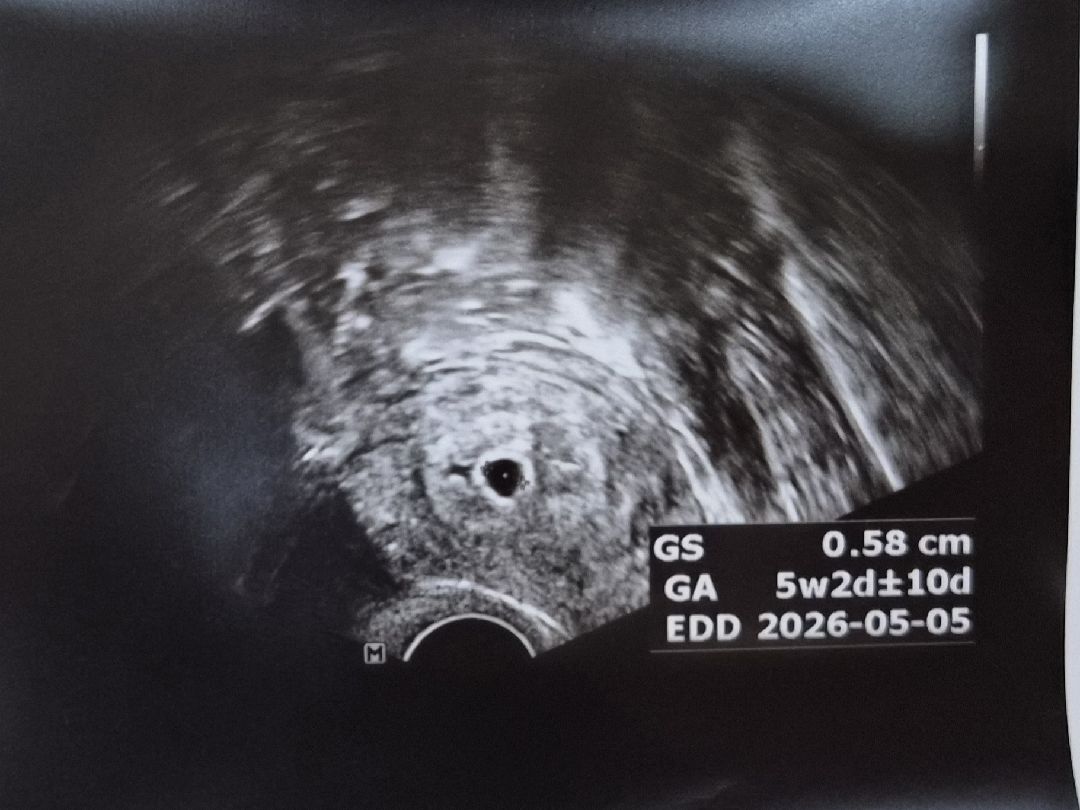

5주차 아기집과 단축근무

4주차때 알게된 날부터 입덧 하다가 이번주는 잠잠해서 불안했었는데 산부인과에서 아기집이 무사히 있는걸 보니 안심되고 행복하네요ㅎㅎ 한편으로는 회사에 임신 알리고 단축시작했는데 몸이 힘들어 업무배제해달라고 말하는게 참 눈치보이고 어렵더라구요ㅠㅠ 아파도 참으며 내일은 다하는 성격인데... 울렁거림에 조금만 일하면 배뭉치고 몇배로 피곤하고 졸리고.. 상상 이상으로 의지대로 몸이 안되니 일하면서 임신 쉽지않네요... 미래 육아까지 생각하면 전초전이겠죠 ㅎㅎ